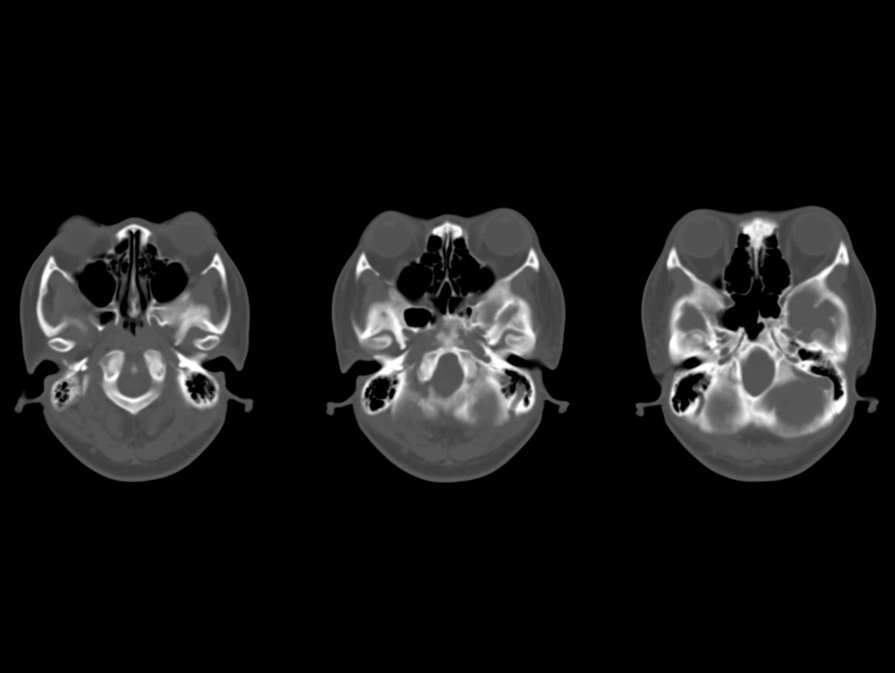

- 図2 頭部CT(骨条件)

大後頭孔の狭窄を認める。

- 頭蓋

前頭部突出(frontal bossing)、頭蓋底の短縮、大後頭孔の狭細化、顔面骨の低形成、下顎骨の突出を認める。